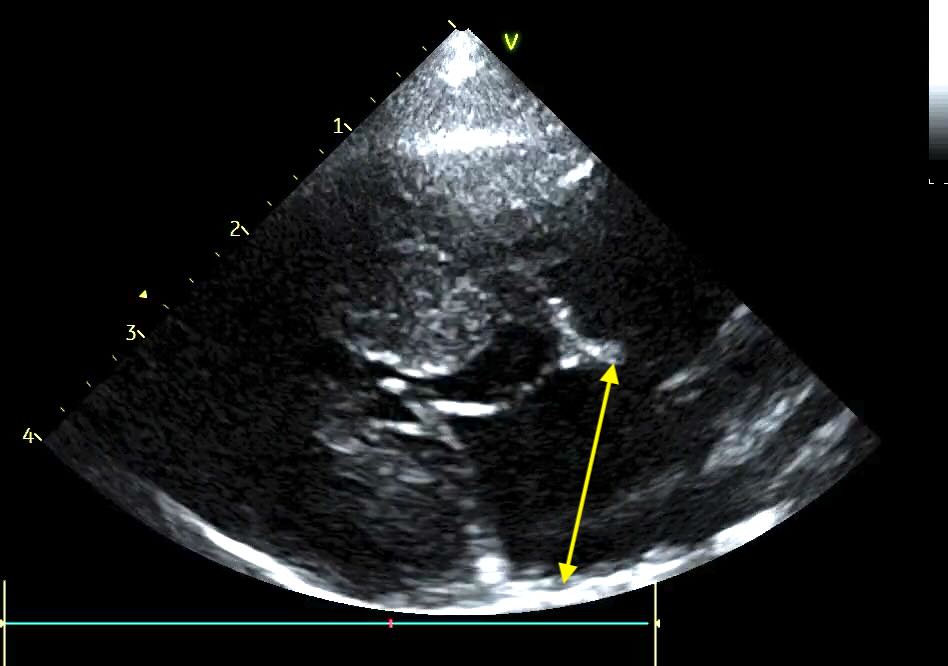

Veterinary cardiology is increasingly moving toward the Left Atrial anteroposterior Dimension (LAD). Measured from the right parasternal long-axis view, the ‘4 Chamber’ view, this metric is often more repeatable, easier to acquire in a struggling patient, and provides a clearer picture of the atrium’s true expansion.

The LAD is measured using the Right Parasternal Long-Axis 4-Chamber view (RPLA4Ch). This is often called the “heart homepage” because it allows for a comprehensive subjective and objective assessment of all four chambers simultaneously. See our article on echo views here.

- Acquisition: With the dog in right lateral recumbency, place the probe at the point of the strongest apical beat. Align the probe parallel to the long axis of the heart, with the transducer mark (and your forefinger) pointed toward the dog’s head.

- Optimisation: Aim to maximise the length of the left ventricle, ensuring the apex is visible and the mitral valve is clearly defined. Avoid any aorta showing (5 chamber view).